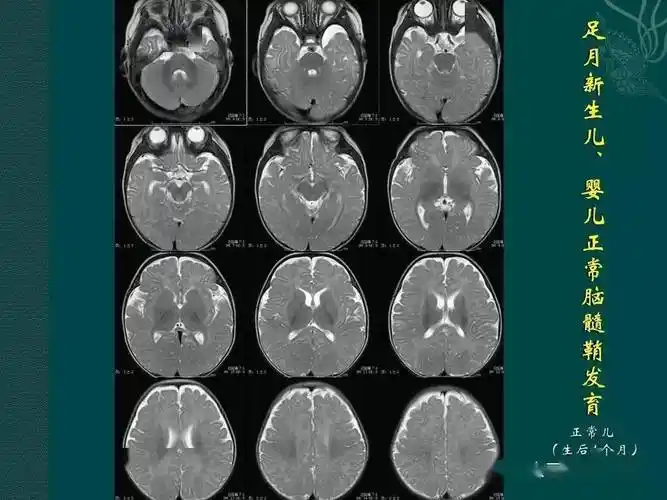

足月儿及婴儿神经系统发育mri